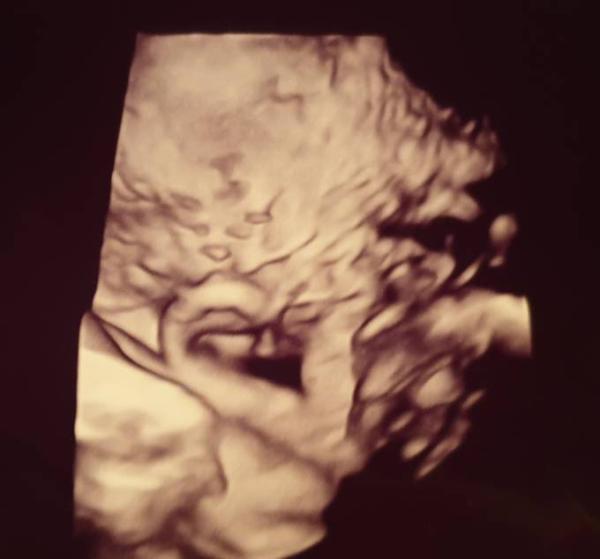

Hallo ihr Lieben, nach dem KH Aufenthalt war heute mein normaler Termin bei der FÄ mit CTG, Blutabnahme und Ultraschall. Auf dem CTG waren ein paar Wehen zu erkennen, die ich auch deutlich gespürt habe. Vor dem Ultraschall hat Sie nach dem Kopf getastet, der schon im Becken liegt aber noch nicht fest. Von daher, gab es heute ein lustiges Foto vom Ohr und den Haaren aufm Kopf Sie wiegt heute bei 37+0 ca. 3115g und am Ende der Woche geht es nochmal in den Kreißsaal zur Kontrolle. Ich fühle mich besser als die letzte Woche und bin nun einfach froh, wenn Sie gesund und munter auf Die Welt kommt, egal wann Ich wünsche Euch allen ganz doll besinnliche Weihnachten mit euren Liebsten und passt schön auf euch auf

Hey auch tolle nachrichten Da kann es ja bei uns bald losgehen Je näher der Termin rückt desto besser fühlt man sich. Die Vorfreude ist soo groß die kleinen Mäuse endlich in den armen halten zu dürfen. Wünschen euch auch schöne Weihnachten und ein baldiges kuscheln mit dem Baby Witziges Bild vom Ohr

Ich musste jetzt mal lachen wegen dem kleinen niedlichen Ohr. Das sieht wirklich echt klasse aus und ich bin jedes mal wieder von neuen begeistert was man schon so alles sieht per Ultraschall. Wirklich wirklich putzig